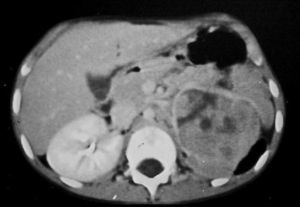

De los pacientes diagnosticados de carcinoma de células renales (n= 4) (con edad y presentación mostrados en la tabla 2) en dos casos se localizaron masas renales en la corteza renal, con infiltración del sistema pielocalicial. De estos dos, uno demostró fuga de contraste del sistema excretor en la radiografía abdominal post-TC con contraste, y el otro invasión de médula con extensión hasta el uréter proximal (fig. 5). En un único caso se apreciaron abundantes calcificaciones grumosas intratumorales dispersas (fig. 6).

Fig. 5. Carcinoma de células renales. (A) Tomografía computarizada abdominal con contraste intravenoso. Corte axial sobre hilios renales. Riñón derecho aumentado de tamaño con discreto retraso de su función. Masa hipodensa central con extensión al sistema colector y escasa captación de contraste. (B) Pielografía ascendente del riñón derecho. En cálices del polo renal superior existe un defecto de repleción junto a dilatación y deformidad por tumoración que ocupa el sistema colector.